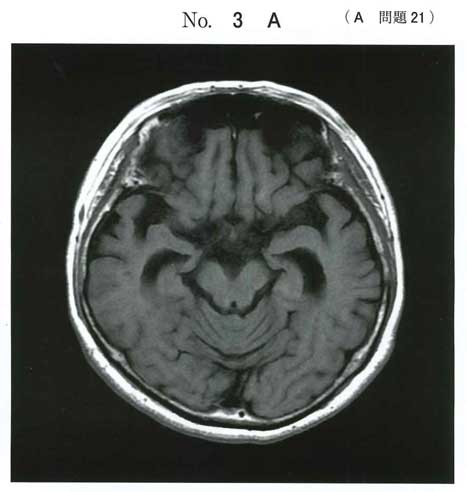

海馬の萎縮でアルツハイマー型認知症。

臨床的にドネペジルがどこまで効くかはさておき。